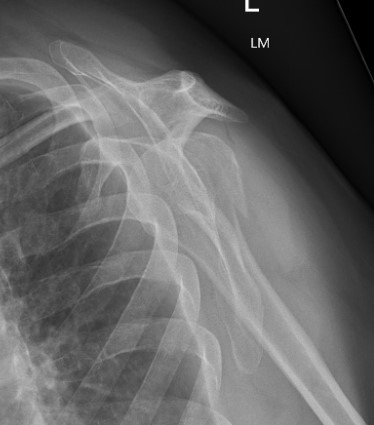

proximal humerus fracture Background ORIF with locking plate Arthroplasty Greater tuberosity fractures Lesser tuberosity fractures / avulsions Book traversal links for Proximal humerus fractures ‹ Pectoralis Major Tears Up Background ›